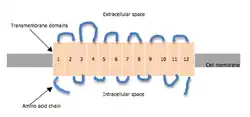

The norepinephrine transporter gene, SLC6A2 is located on human chromosome 16 locus 16q12.2. This gene is encoded by 14 exons.[7] Based on the nucleotide and amino acid sequence, the NET transporter consists of 617 amino acids with 12 membrane-spanning domains. The structural organization of NET is highly homologous to other members of a sodium/chloride-dependent family of neurotransmitter transporters, including dopamine, epinephrine, serotonin and GABA transporters.[7]

The norepinephrine transporter is composed of 12 transmembrane domains (TMDs). The intracellular portion contains an amino (-NH

2) group and carboxyl (-COOH) group. In addition, there is a large extracellular loop located between TMD 3 and 4.[14][6][15] The protein is composed of 617 amino acids.[14]